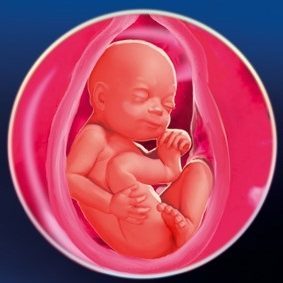

Чи не так довго залишається чекати до зустрічі мами зі своїм малятком. На 28 тижні вагітності, навіть у разі виникнення неприємних несподіванок, народжені передчасно, мають всі шанси на довге і щасливе життя.

Виживання крихіток на цьому терміні вселяє оптимізм, адже до 28-го тижня передчасні пологи вважаються викиднем.

28 тиждень вагітності розвиток плода: що потрібно знати, на що звернути увагу?